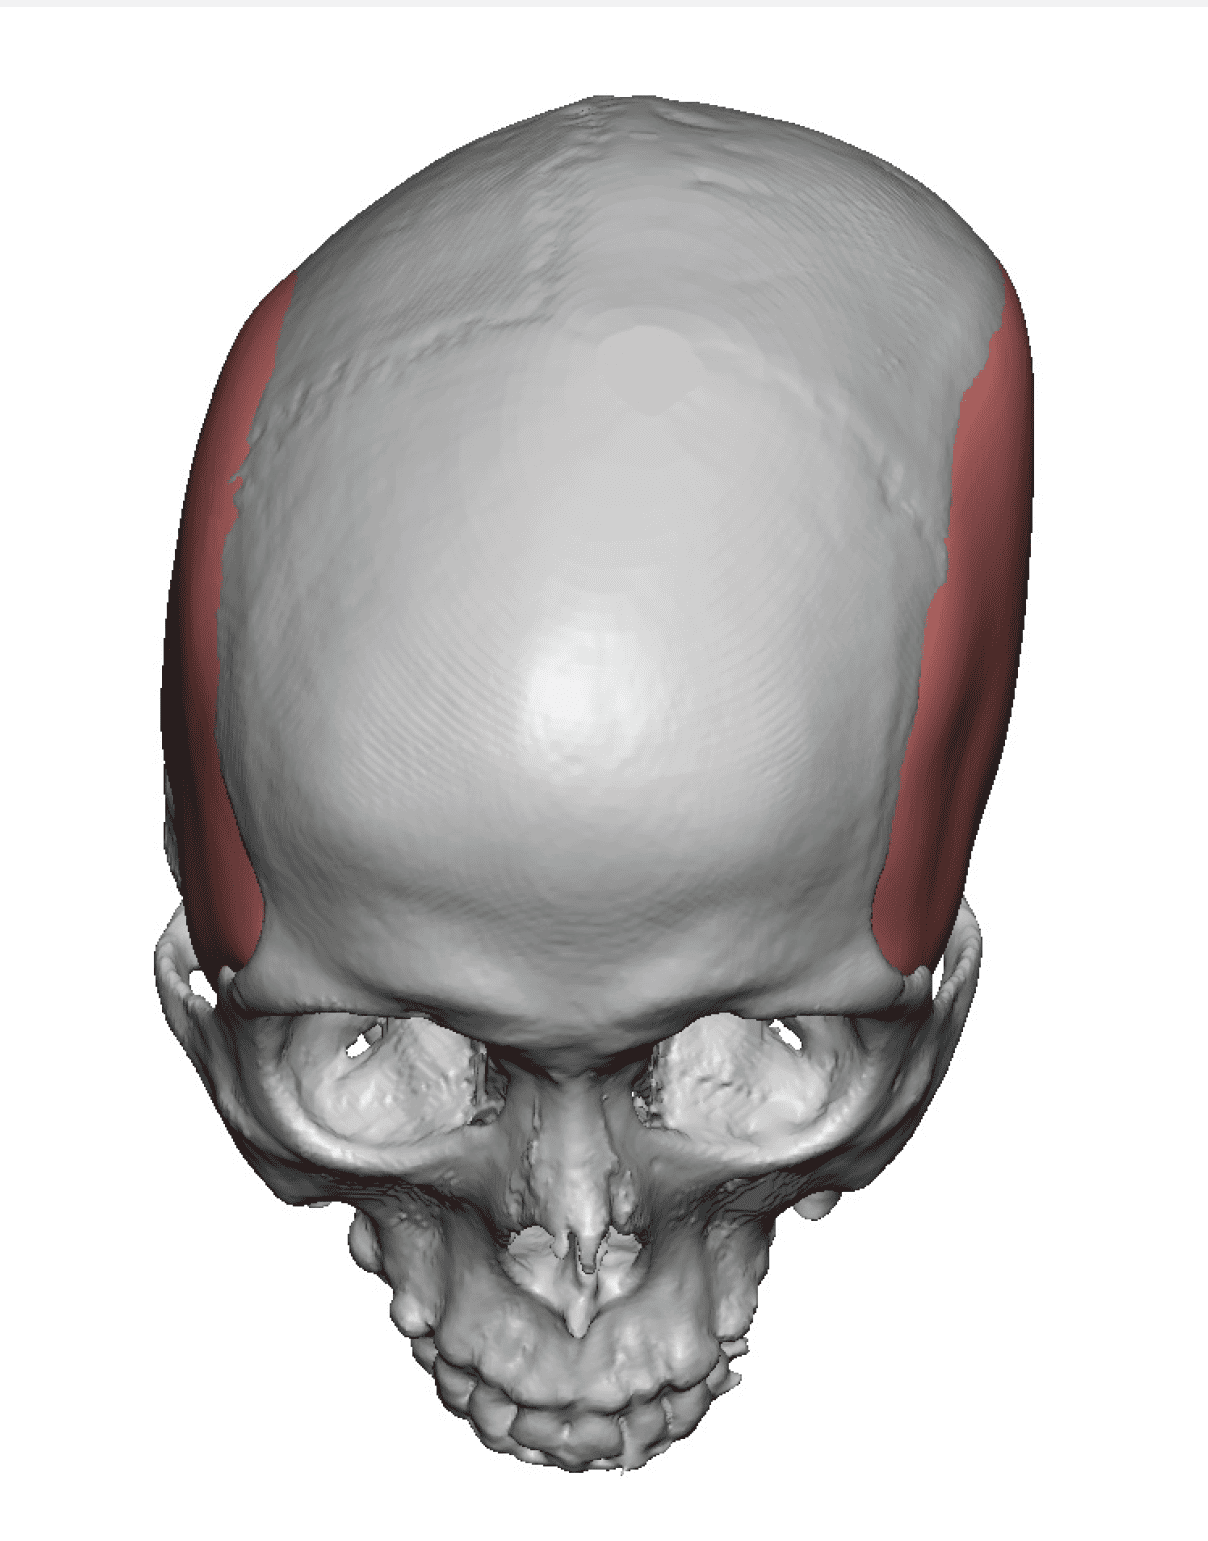

Patient 28

Desire for rounder shape to the top of the head from a congenital parasagittal deficiency skull shape.

Custom skull implant designed to fill in the parasagittal deficiencies.

Desire for rounder shape to the top of the head from a congenital parasagittal deficiency skull shape.

Custom skull implant designed to fill in the parasagittal deficiencies.